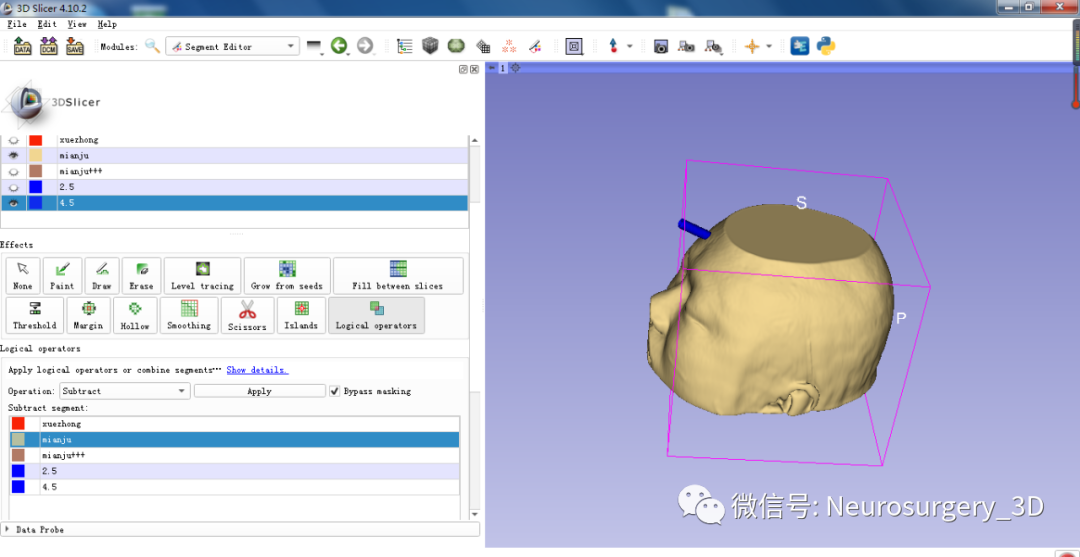

3、利用Logical operators逻辑运算模块中相减功能得出头颅面具模型。

二)利用Logical operators逻辑运算模块的复制、相减功能生成面具模型

3、利用Logical operators逻辑运算模块复制头颅原始模型并扩大。

4、再次利用Logical operators逻辑运算模块,运算后重建出面具三维模型

运算后结果

4、生成穿刺导板面具

5、修剪需要打印的穿刺导板